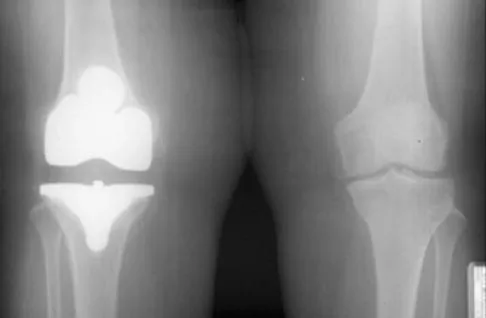

Question 260High Yield

Figure 10 shows the AP radiograph of an ambulatory 76-year-old patient. What is the most appropriate surgical treatment option for this patient?

Explanation

The patient has a periprosthetic fracture around a loose cemented femoral component. The proximal bone stock is poor; therefore, this fracture may be categorized as Vancouver 3-B. Hip arthrodesis and resection arthroplasty provide suboptimal results, particularly for ambulatory patients. Although impaction allografting may be an option to restore the bone stock in a younger patient, the latter procedure will be very difficult to perform when the proximal bone is poor in quality and fractured. Cementing another component into this wide femur is not an option. The best option for revision of the femoral component in this elderly patient is proximal femoral replacement arthroplasty. Malkani AL, Settecerri JJ, Sim FH, et al: Long-term results of proximal femoral replacement for non-neoplastic disorders. J Bone Joint Surg Br 1995;77:351-356.